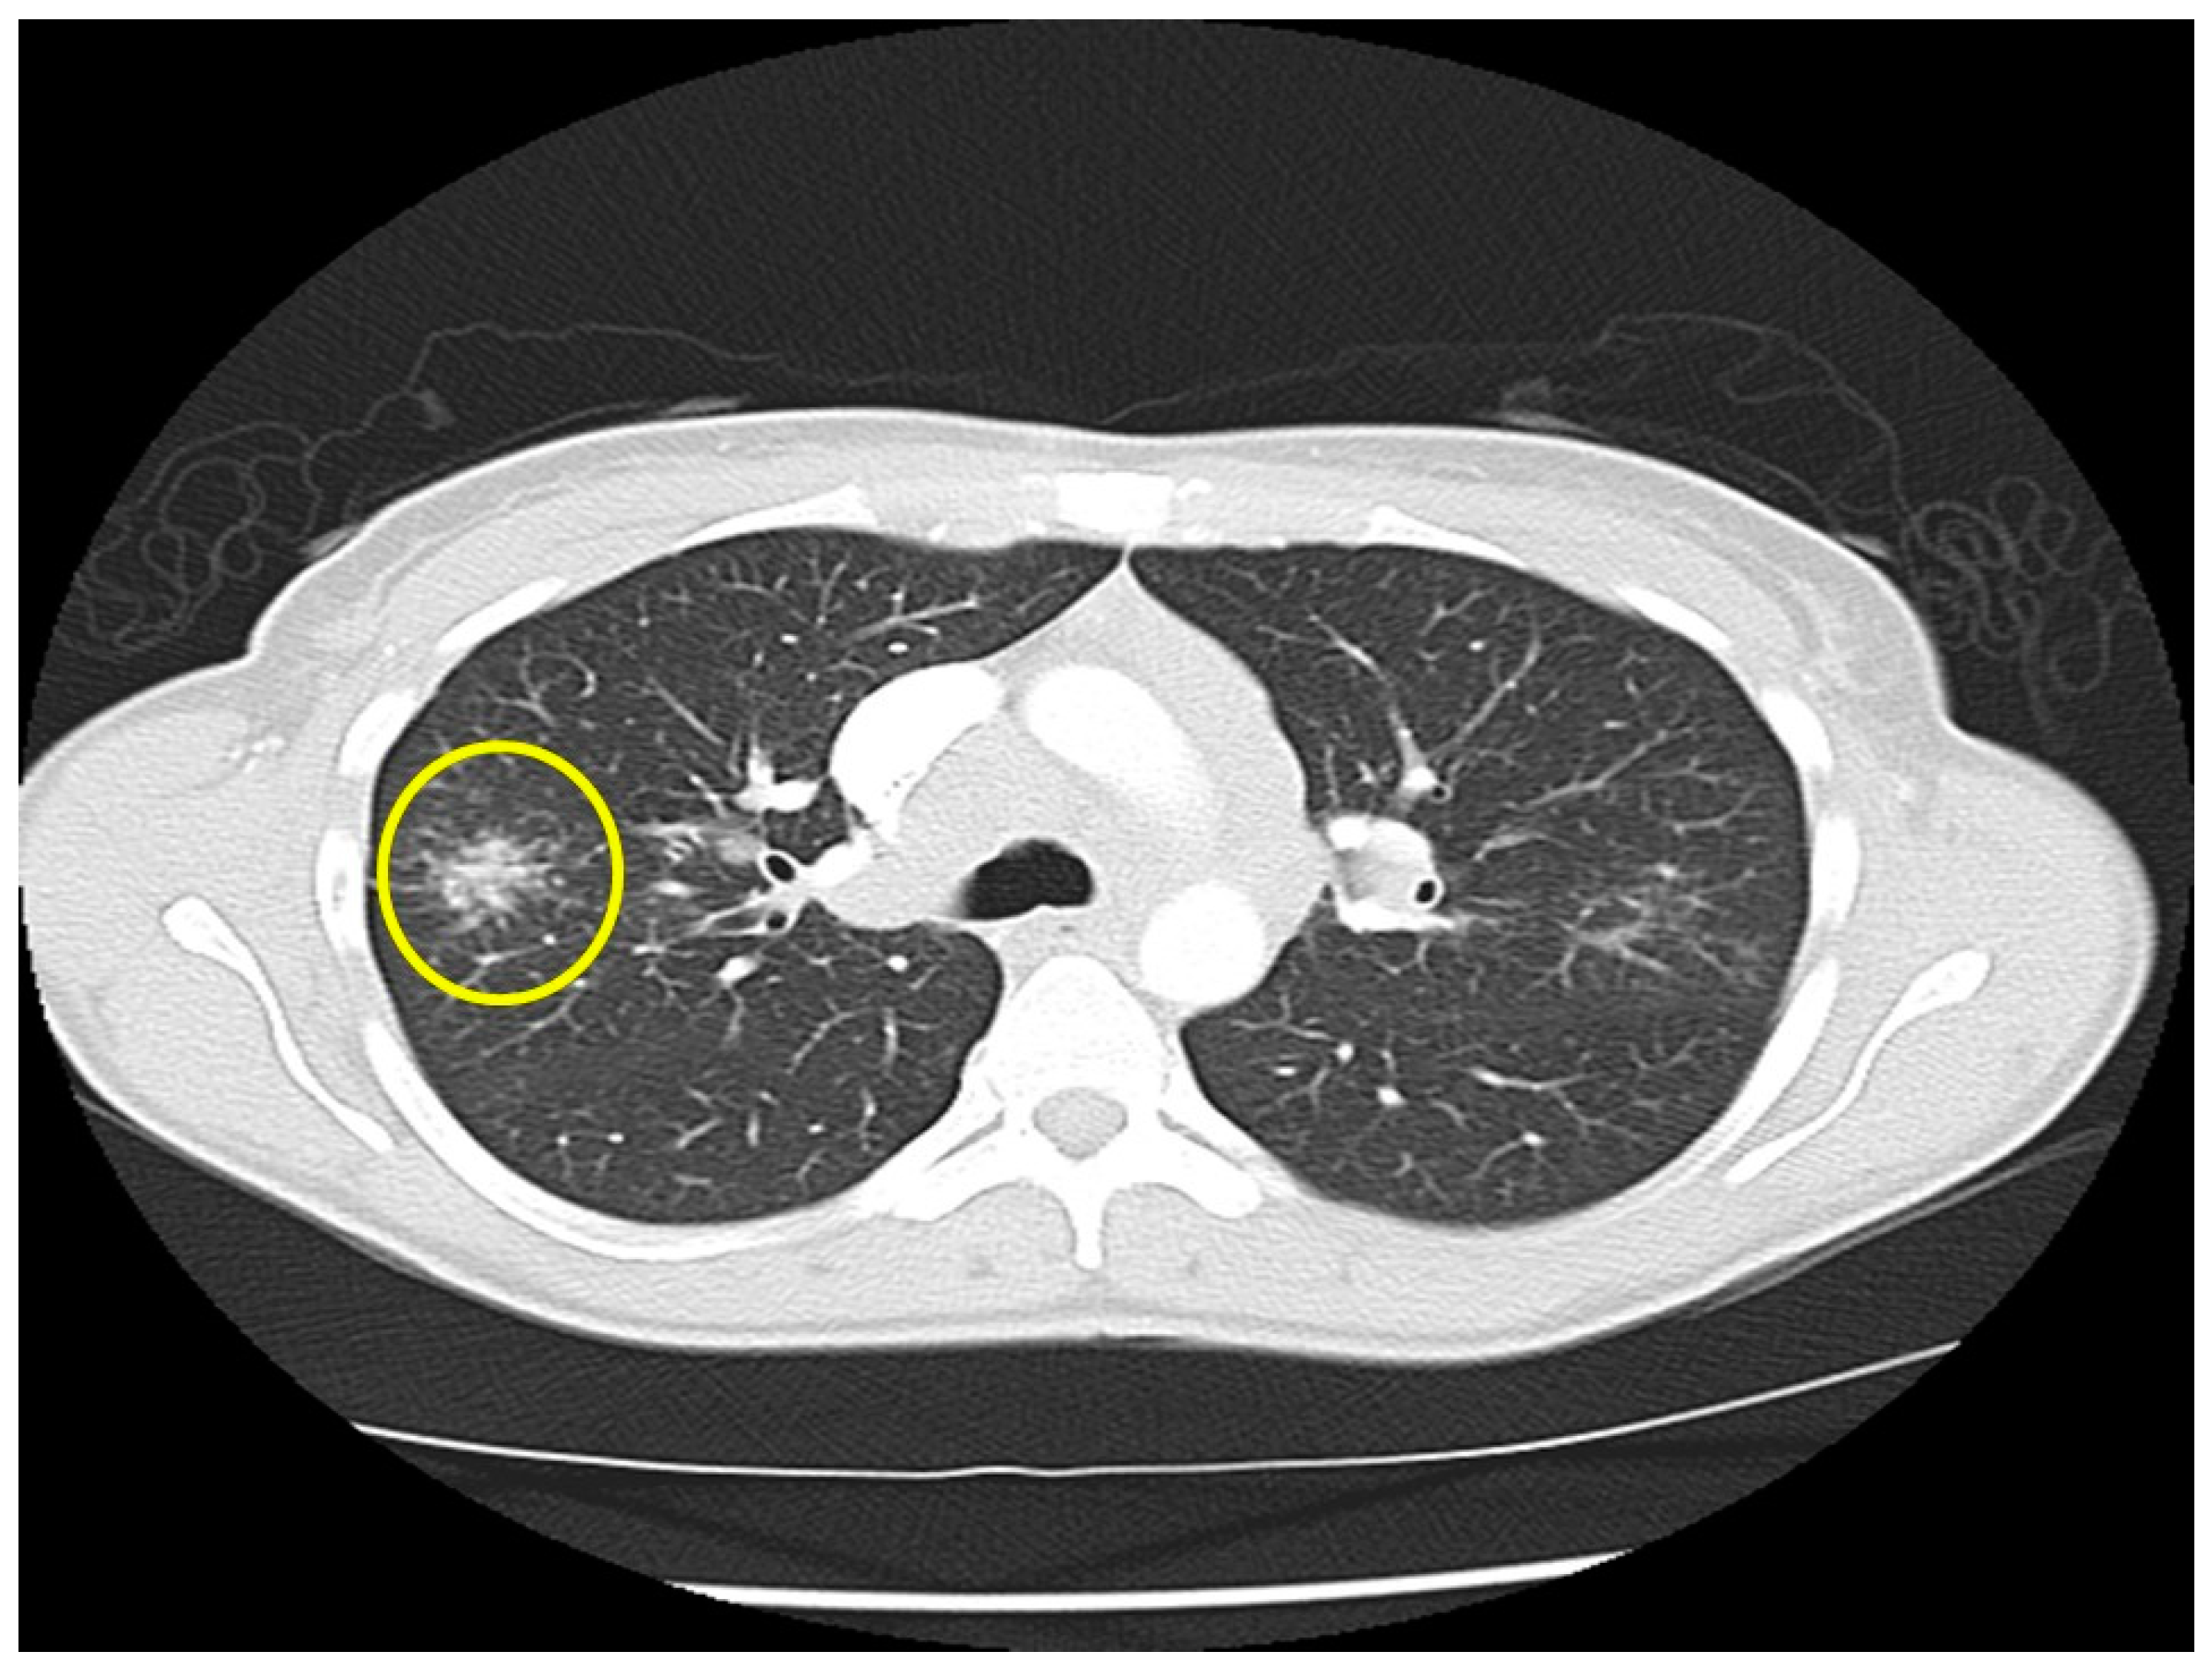

Figure 5.

Chest CT image of a “galaxy sign” in a patient with pulmonary sarcoidosis. Micronodules coalescence into a central mass-like lesion (within circle).